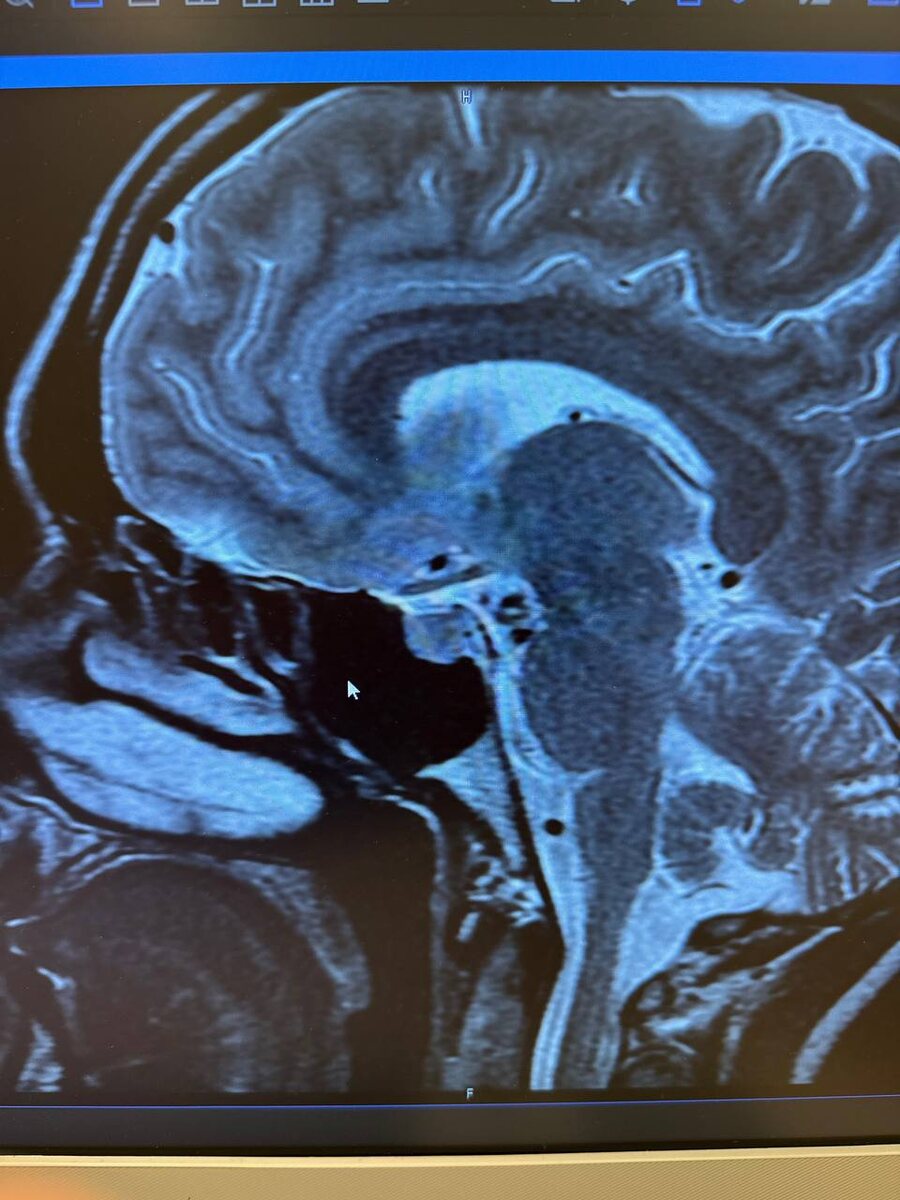

Первое, что надо сделать при повышенном пролактине - МРТ гипофиза с контрастом. И конечно догадки подтвердились оказалась аденома, которая сдавливает гипофиз и вырабатывает много пролактина.